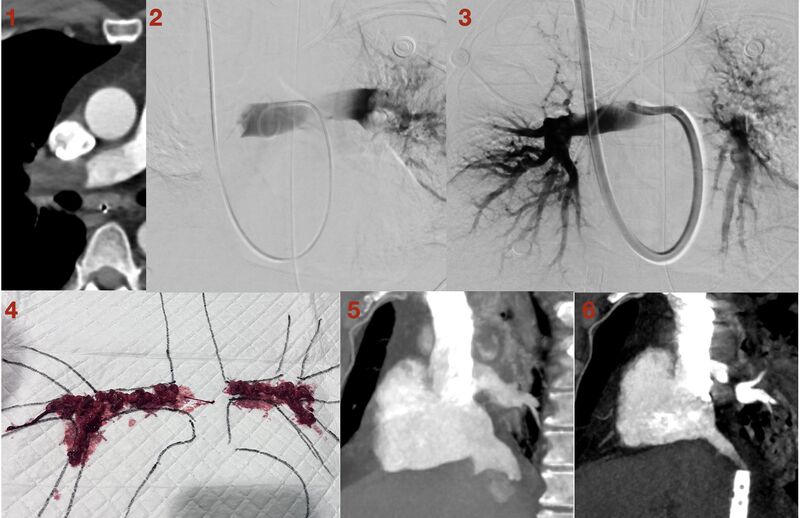

- 影像线索: 转院前腹部 CT 显示:肾细胞癌(RCC)伴下腔静脉(IVC)癌栓,癌栓已向上延伸至肝上 IVC。这提示肺部的阻塞物极可能是“肿瘤栓子”。

- 造影: 右肺动脉及左下叶动脉完全闭塞。

- 操作: 经颈静脉入路,使用 Penumbra Flash 16 抽吸系统。正如预料,这些“血栓”极其坚硬,耗费了大量时间才将其破碎抽出。最终血流恢复,心脏负荷明显缓解。

- 病理证实: 抽吸出的组织证实为透明细胞肾细胞癌。

作者在反复对比 ECMO 置管前后的影像(图5、图6)后,发现了一个惊人的细节: 由于下腔静脉内充满肿瘤组织,ECMO 导管的侧孔几乎全部被埋在了肿瘤内部被堵死。这导致 ECMO 强大的负压吸引力全部集中在了唯一畅通的导管尖端! 这种极端的局部负压吸附在右心房壁上,极有可能直接导致了心房壁的撕裂与心包积血。